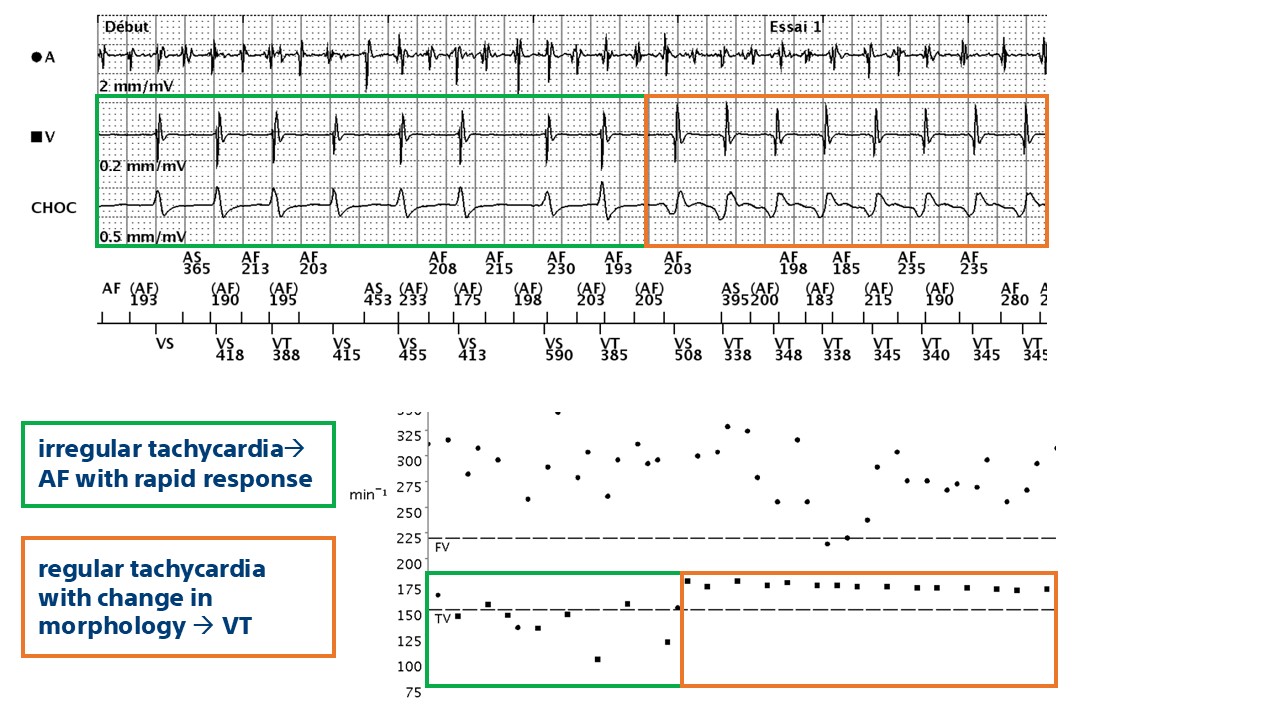

- this trace shows the value of coupling discriminators for the diagnosis of complex tachycardias such as dual tachycardias; discrimination is performed in stages

- in this example, the device finds a diagnosis of AF with a stable rhythm (diagnosis of dual tachycardia) and therapies are delivered

This tracing shows a characteristic appearance of dual tachycardia (AF + VT): atrial activity is rapid and polymorphic (cycles correctly classified as AF); the ventricular channel shows abrupt acceleration with a regular, monomorphic tachycardia with a clear change in signal morphology on the shock channel (VT); the device diagnoses double tachycardia (V>A: False, RID-, AF, stable rhythm) and delivers therapies.